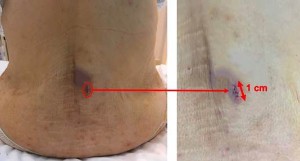

mà del Dr. Morgenstern (esquerra). Cal observar la incisió mínima en la pell de

menys d’1 cm de longitud i l’absència de sagnat de la ferida

Imatges postoperatòries de la ferida d’1 cm de longitud (fletxa vermella). Al voltant de la ferida es pot veure un petit hematoma (color blau) que desapareix als pocs dies després de la cirurgia.